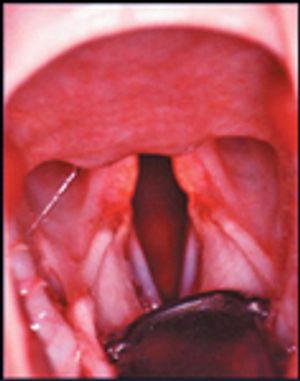

The tie back remains the most common surgical method for correction.

Laryngeal paralysis is recognized because of the loss of function in the paired cricoarytenoideus dorsalis (CAD) muscles, which are the only abductors of the aytenoid cartilages.